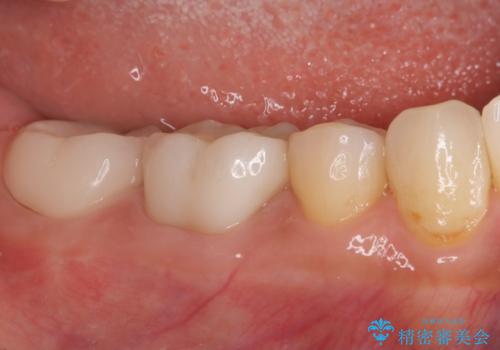

ズキズキ痛い歯 オールセラミッククラウンによる修復

- 冷たいもので長引く痛みがあることを主訴に来院されました。

抜髄を行い、オールセラミッククラウンにて修復を行いました。

- 26万円費用は治療当時の料金となります

根管充填はバイオセラミックシーラーを使用しています。